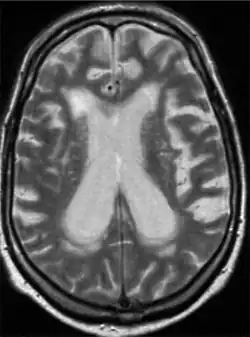

Individual infected with Mycobacterium caprae -Non-contrast MRI of brain shows slight atrophy, ventricular enlargement and cerebral microangiopathy